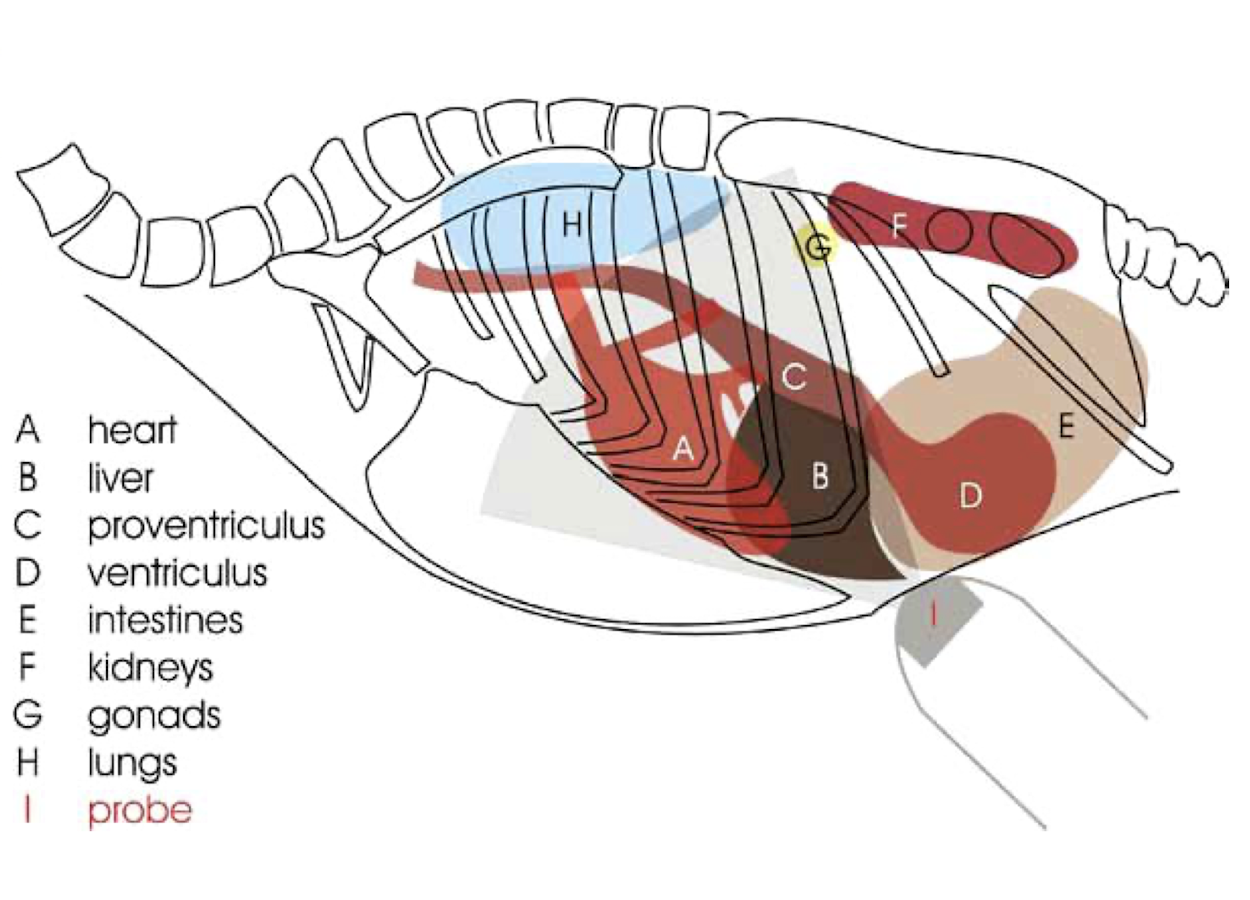

GI tract

Lack of ultrasound windows due to the keel and air sacs → mostly just for echocardiography

Which organs are rarely visualized with ultrasonography in birds?

Kidneys, gonads (unless large), and spleen.

What is a key advantage of endoscopy in birds for diagnostic purposes?

It allows direct visualization of all abdominal and thoracic organs without the need for insufflation and enables targeted biopsies. use a 2.7mm 30o endoscope!